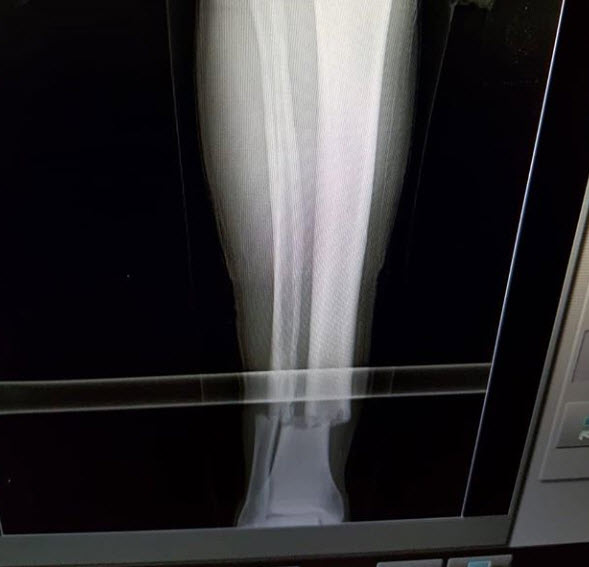

Spor sakatlıkları, sporcuların korkulu rüyası. Hafif sakatlıklar dahi sorun yaratırken, yaşanan bu sakatlar yürekleri burkuyor. Sporun doğasında olan ancak sporcuların kariyerlerini bitirme noktasına gelen bu sakatlıklar arasında kırılan ayaklardan, yarılan kafalara kadar, bakmaya bile cesaret edemeyeceğiniz sakatlıklar yer alıyor.

SPOR TARİHİNE GEÇEN EN KORKUNÇ SAKATLIKLAR

The Coventry defans oyunucusu David Busst, Nisan 1996'da Manchester United'ın defans oyuncusu Denis Irwin ile çarpışması sonucu incik kemiği ve kaval kemiğini kırmıştı. Kırılan kemiğin deriyi delmesinden dolayı akan kanı sahadan temizlemeleri gerekmişti. Busst bir daha profesyonel olarak oynayamadı. United'ın kalecisi Peter Schmeichel, kazanın görgü tanığı olarak, sonrasında psikolojik tedavi görmüştü.